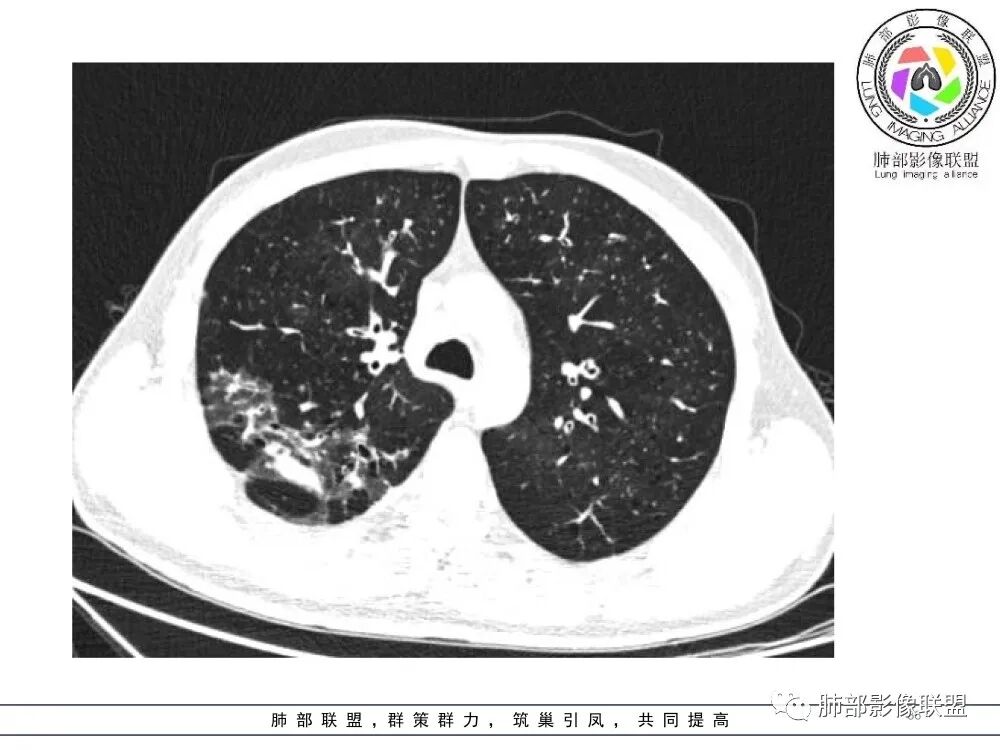

肺部影像联盟晨读病例肺气肿,多发气管壁增厚,片状影,符合气道分布,考虑气道侵袭性曲霉菌病。

中年男性,慢性咳嗽,有吸烟史,胸部CT基础尚可,双肺多发的沿支气管播散的树芽影以及支气管管壁的增厚和对应区域内的斑片影实变影,符合气道播散的表现。经过对症抗感染治疗1月之后,胸部CT影像进展。右侧播散到左侧。实变和漱牙以及气管壁增厚均较前明显进展。

2.胸部CT:两肺广泛的支扩,支气管壁增厚,多发的树芽影,部分伴有支气管周围的渗出,少量实变。不足一月复查,原有支扩、支气管壁增厚基础上伴有大量渗出,实变,结节,胸膜下累及。

3.综合分析:首先病灶沿支气管分布,呈树芽征及实变影,相应支气管壁广泛增厚,其次病变范围比较广泛,几乎累及所有叶段,这种表现常高度提示气道播散,经过对症抗感染治疗20多天后,胸部CT影像明显进展。符合IPA的进展表现。